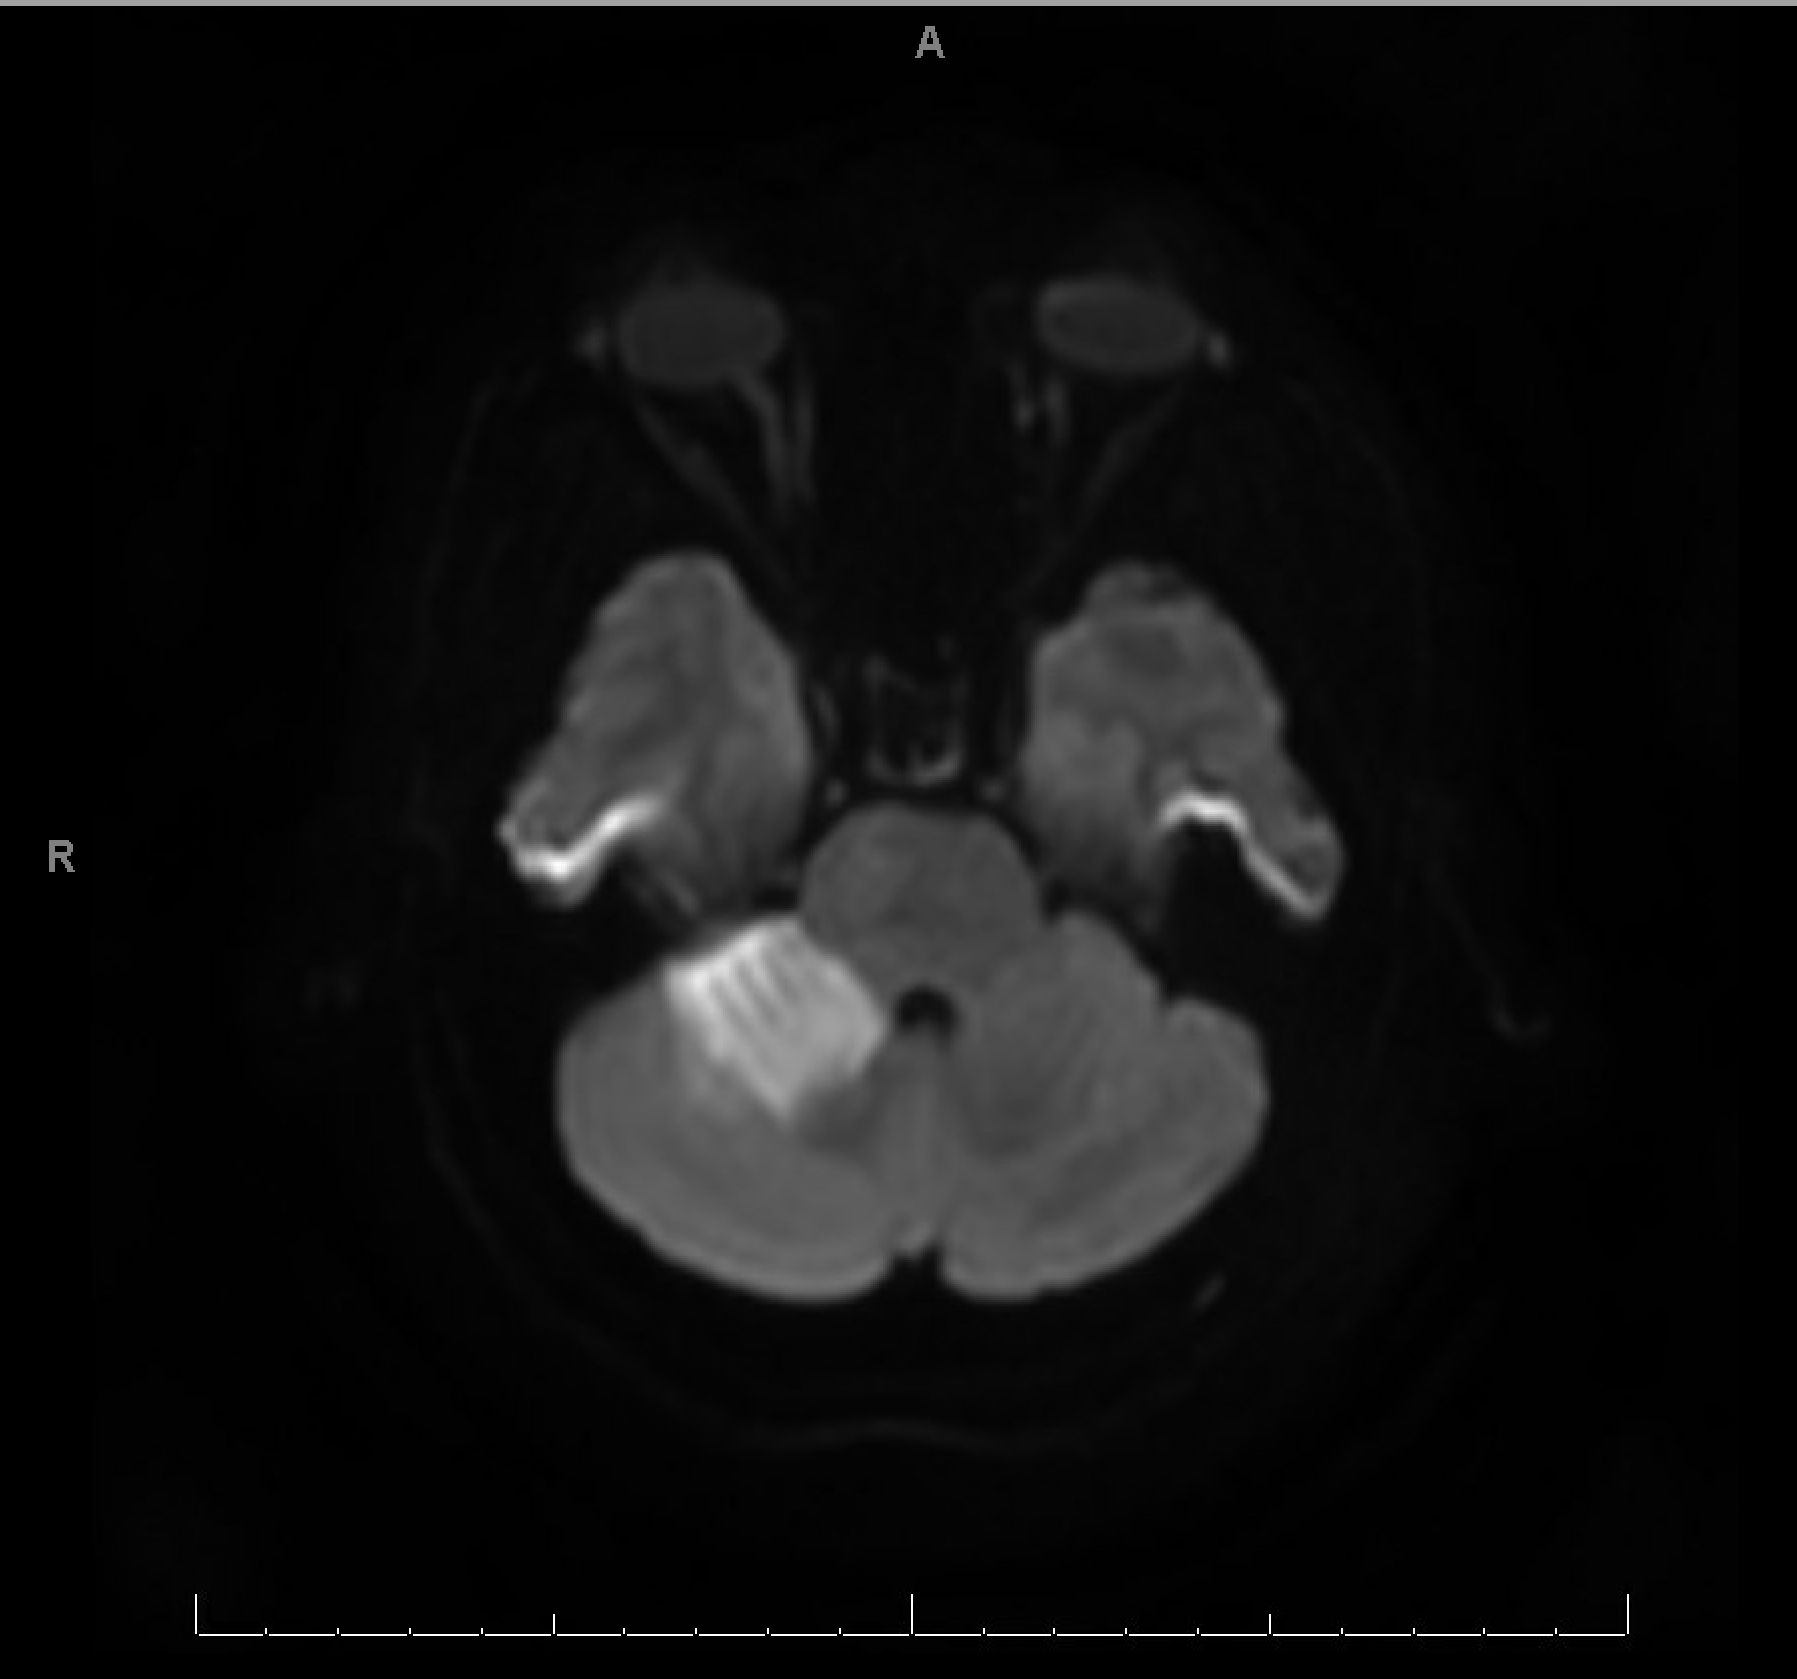

CTA revealed bilateral PCA stenosis, likely due to vasospasm. MRI brain showed bilateral occipital, left mesial temporal, and right cerebellar vasogenic edema with areas of restricted diffusion and microhemorrhages, supporting the diagnosis of PRES. Workup for infection, vasculitis, and autoimmune encephalitis was negative. Hypertensive emergency was suspected as the precipitating factor.

This case underscores the diagnostic complexity of PRES, which can mimic stroke, infection, or structural lesions. Imaging, particularly MRI, is pivotal in distinguishing PRES from infarction. The presence of seizures, encephalopathy, and visual disturbances in the setting of malignant hypertension should prompt immediate consideration of PRES, especially when imaging suggests posterior white matter involvement. This case highlights the urgency of BP control and the need for a multidisciplinary approach, including neurology, radiology, and critical care, to prevent long-term neurological sequelae.